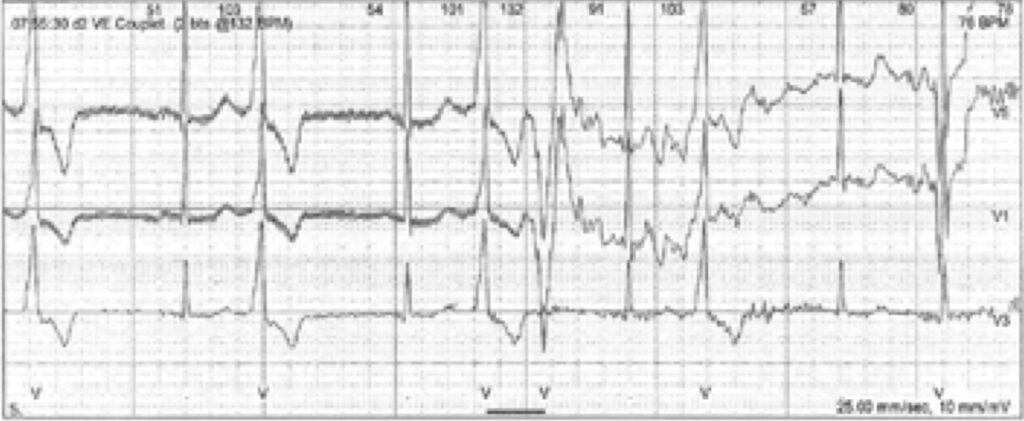

心電図所見

典型的なQT延長ではないですが著明なU波と特徴的なニ方向性心室期外収縮が見られます。

ニ方向性心室期外収縮

ニ方向性心室期外収縮およびニ方向性心室頻拍が見られます。